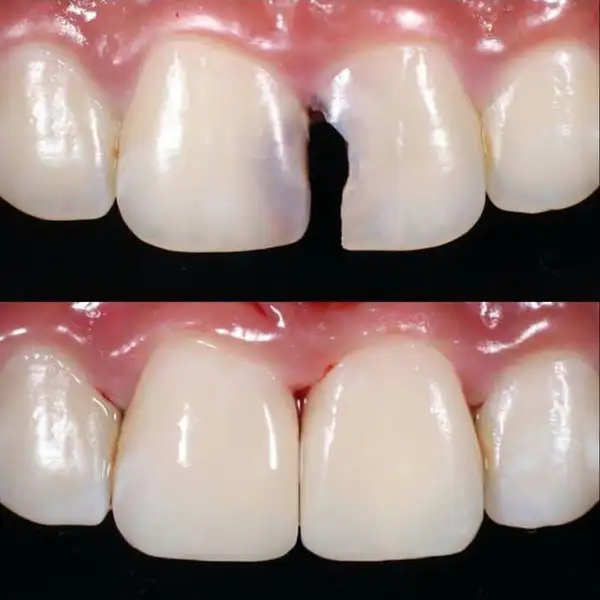

3. Tooth-Coloured Fillings

Natural-looking, mercury-free fillings that restore decayed or damaged teeth while maintaining strength and aesthetics. They bond strongly to the tooth structure and prevent further decay. These fillings are ideal for both front and back teeth and provide long-lasting protection with a natural appearance.